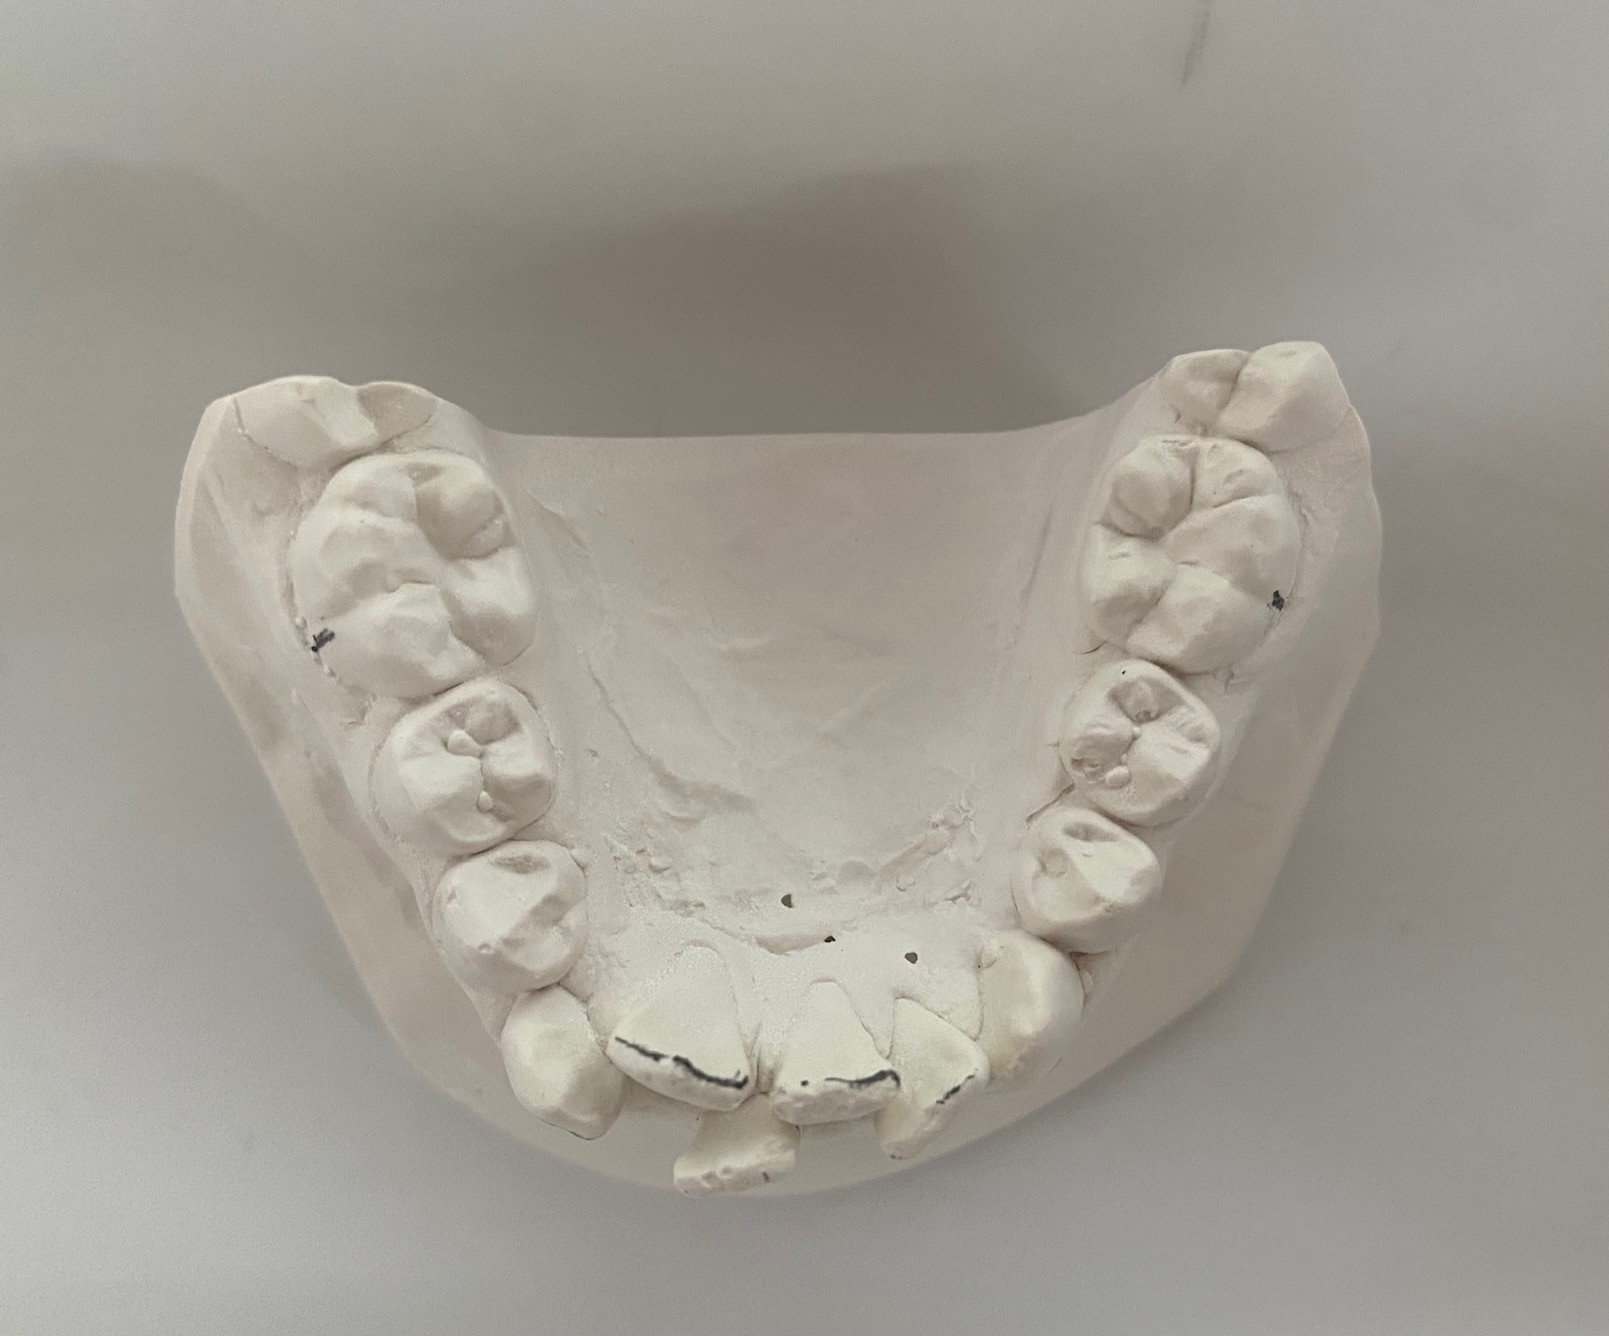

Oppstart med dokumentasjon

Vi tar nødvendige røntgenbilder, foto og kliniske modeller/skanninger. Dette danner det faglige grunnlaget for en individuell behandlingsplan og sikrer korrekt beregning av refusjon fra Helfo.